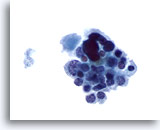

Onbepaalbaar voor maligniteit

Deze catergorie omvat in ons lab ook monsters waarvan de voorspellende waarde van maligniteit bij histologie minder dan 50% is (meestal minder dan 30%) en hoger dan 10%.[6, 7] Dit omvat die monsters die een paar kenmerken vertonen van papillair carcinoom, maar die onvoldoende zijn voor een diagnose. [7] De positieve voorspellende waarde hiervan varieert in de literatuur van 20 tot 54%. [7, 9, 10, 11] Deze laesies vertegenwoordigen vaak de folliculaire variant van papillair carcinoom. In deze diagnostische categorie vallen ook folliculaire en Hürthle celneoplasma’s, die worden gekenmerkt door weinig colloïde en folliculaire cellen in microfollikels en opeengepakte groepen of losse Hürthle-cellen. De positieve voorspellende waarde van deze laesies voor een carcinoom varieerde in de literatuur van 2 tot 91%,[6, 9, 10, 12, 13, 14, 15, 16, 17, 18, 19, 20, 21, 22, 23, 24, 25, 26, 27]waarschijnlijk als gevolg van verschillende definities van deze termen en wisselende criteria die worden gebruikt voor het schema en bij de histologische diagnose. Bij de meeste rapporten is deze waarde minder dan 30%. [10, 15, 22, 24, 27]